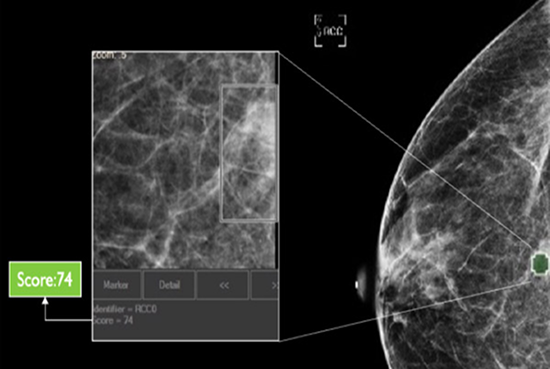

cmAssist has the ability to quickly detect key regions of interest on a mammogram, and accurately quantify and label anomalies as suspicious or, instead, verifiably benign. cmAssist does this by searching all the views of a digital 2D-mammogram for abnormal areas of density, mass or calcification and by highlighting suspicious areas requiring further analysis. Once anomalies are flagged in the system, cmAssist then marks the mammogram and highlights the identified anomalies.

The software also generates a unique, data-driven neuScore™ that provides radiologists with a quantitative measure of suspiciousness in a marked region of interest, ranging from 0 (least suspicious) to 100 (highly suspicious). This score can be tracked over time to evaluate the stability or evolution of identified anomalies.